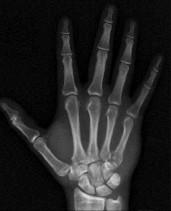

الفحوصات التصويرية (Imaging Studies):

- الأشعة السينية (X-rays): هي الخطوة الأولى في تقييم الكسور، الخلوع، وتغيرات التهاب المفاصل. تساعد في تحديد مدى تدهور العظام والمسافات المفصلية. على سبيل المثال، تُظهر صور الأشعة السينية كسور السلاميات

، بالإضافة إلى علامات مثل "الدمعة الشعاعية" (Radiographic Teardrop) في الرسغ التي تمثل الزاوية الزندية الراحية الحرجة للكعبرة البعيدة